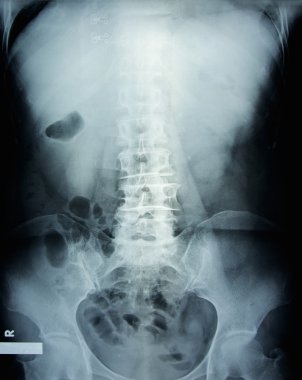

Sırt ve kereste omurgasının röntgen ışınları spondilotik değişimleri, sırt ve kereste dikenlerinin düzleştirilmesini, omurgalar arası disk alanlarının bozulmamış olduğunu, sırt ve kereste dikenlerinin Spondylosis 'inin bozulmamış olduğunu gösterir.